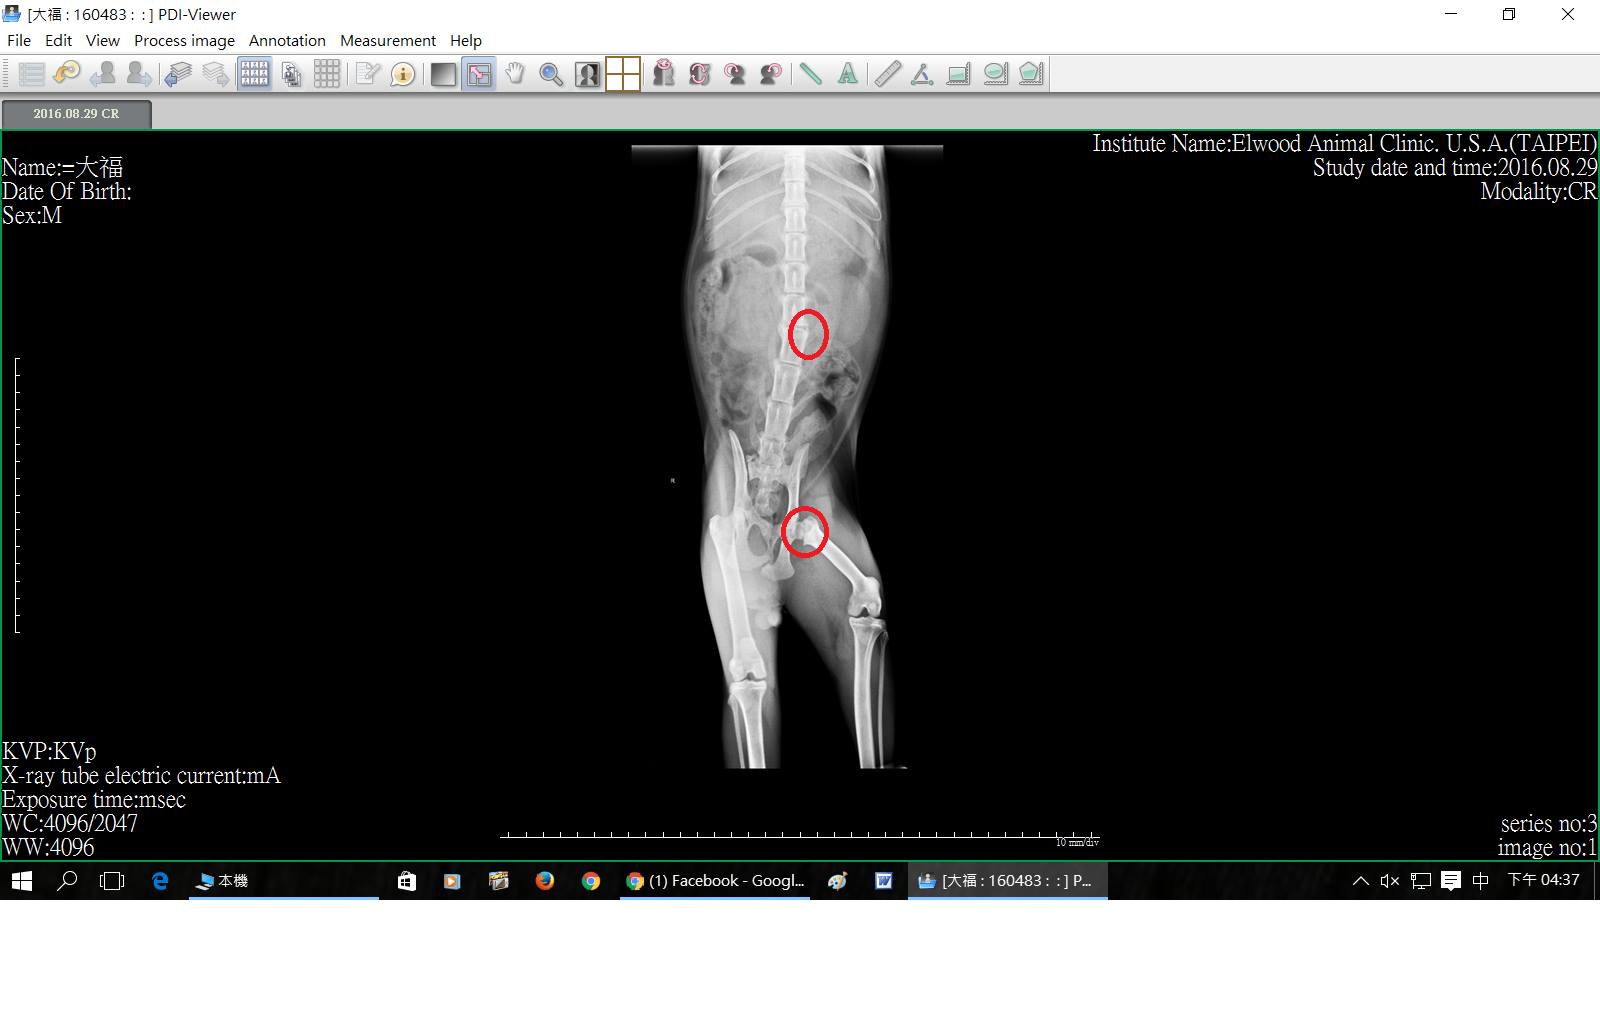

主題: 因股骨頸骨折進行髖關節移除手術的大福 申請者姓名: 臺北市支持流浪貓絕育計劃協會 花色: 申請日期: 2016-09-29 11:57:52 申請者部落格: 申請者臉書網址: 所在縣市/合作醫院: 台北市/其他院所醫助專案(醫院請先MAIL溝通) 治療費用: 33500元 需求人數: 35人 已結案 (2016-12-21 02:01:29) 報名人員: 韋年(已付款)、ying(已付款)、HsiaoWei Sung x2(已付款)、Yiying Liu(已付款)、Ariel Chen(已付款)、Sophie chang(已付款)、PhoebeWang(已付款)、Chris Lin(已付款)、薇薇安(已付款)、林嘉南(已付款)、Melody Tsai(已付款)、Melody Tsai x5(已付款)、Tetsu x2、呼嚕愛草莓 x2、優遊 x2(已付款)、Hikaru OH(已付款)、Selene Tsai(已付款)、小U、燁、Kun-Xiang Zhan(已付款)、cc-ninomi(已付款)、Gina Ji(已付款)、Ting Huang(已付款)、Olivia Hsin-Ling Cho(已付款)、a-song(已付款)、Amber Chung(已付款)、恩客(已付款)、麥克(已付款)、麥克 x3(已付款)、小U(已付款)、鍾瓜瓜(已付款)、 候補人員: 動物病情說明: 大福是來自樹林的街貓,

醫生認為大福的左後腿會自己動,

但右後腿的狀況比較差,

若都不管他大福可能就會自己放棄使用自己的後腿,

後腿則會漸漸地萎縮最終真的變成癱瘓無法使用,

建議可以幫助大福復健、維持可動性。

但在進行復健之前,

因醫生診斷出大福有左側股骨頸骨折的問題,

導致大福在某些動作時會有疼痛的情況,

所以醫生建議可先施行左側股骨頭頸切除手術,

這樣在之後的復健、針灸等會有較佳的療效。